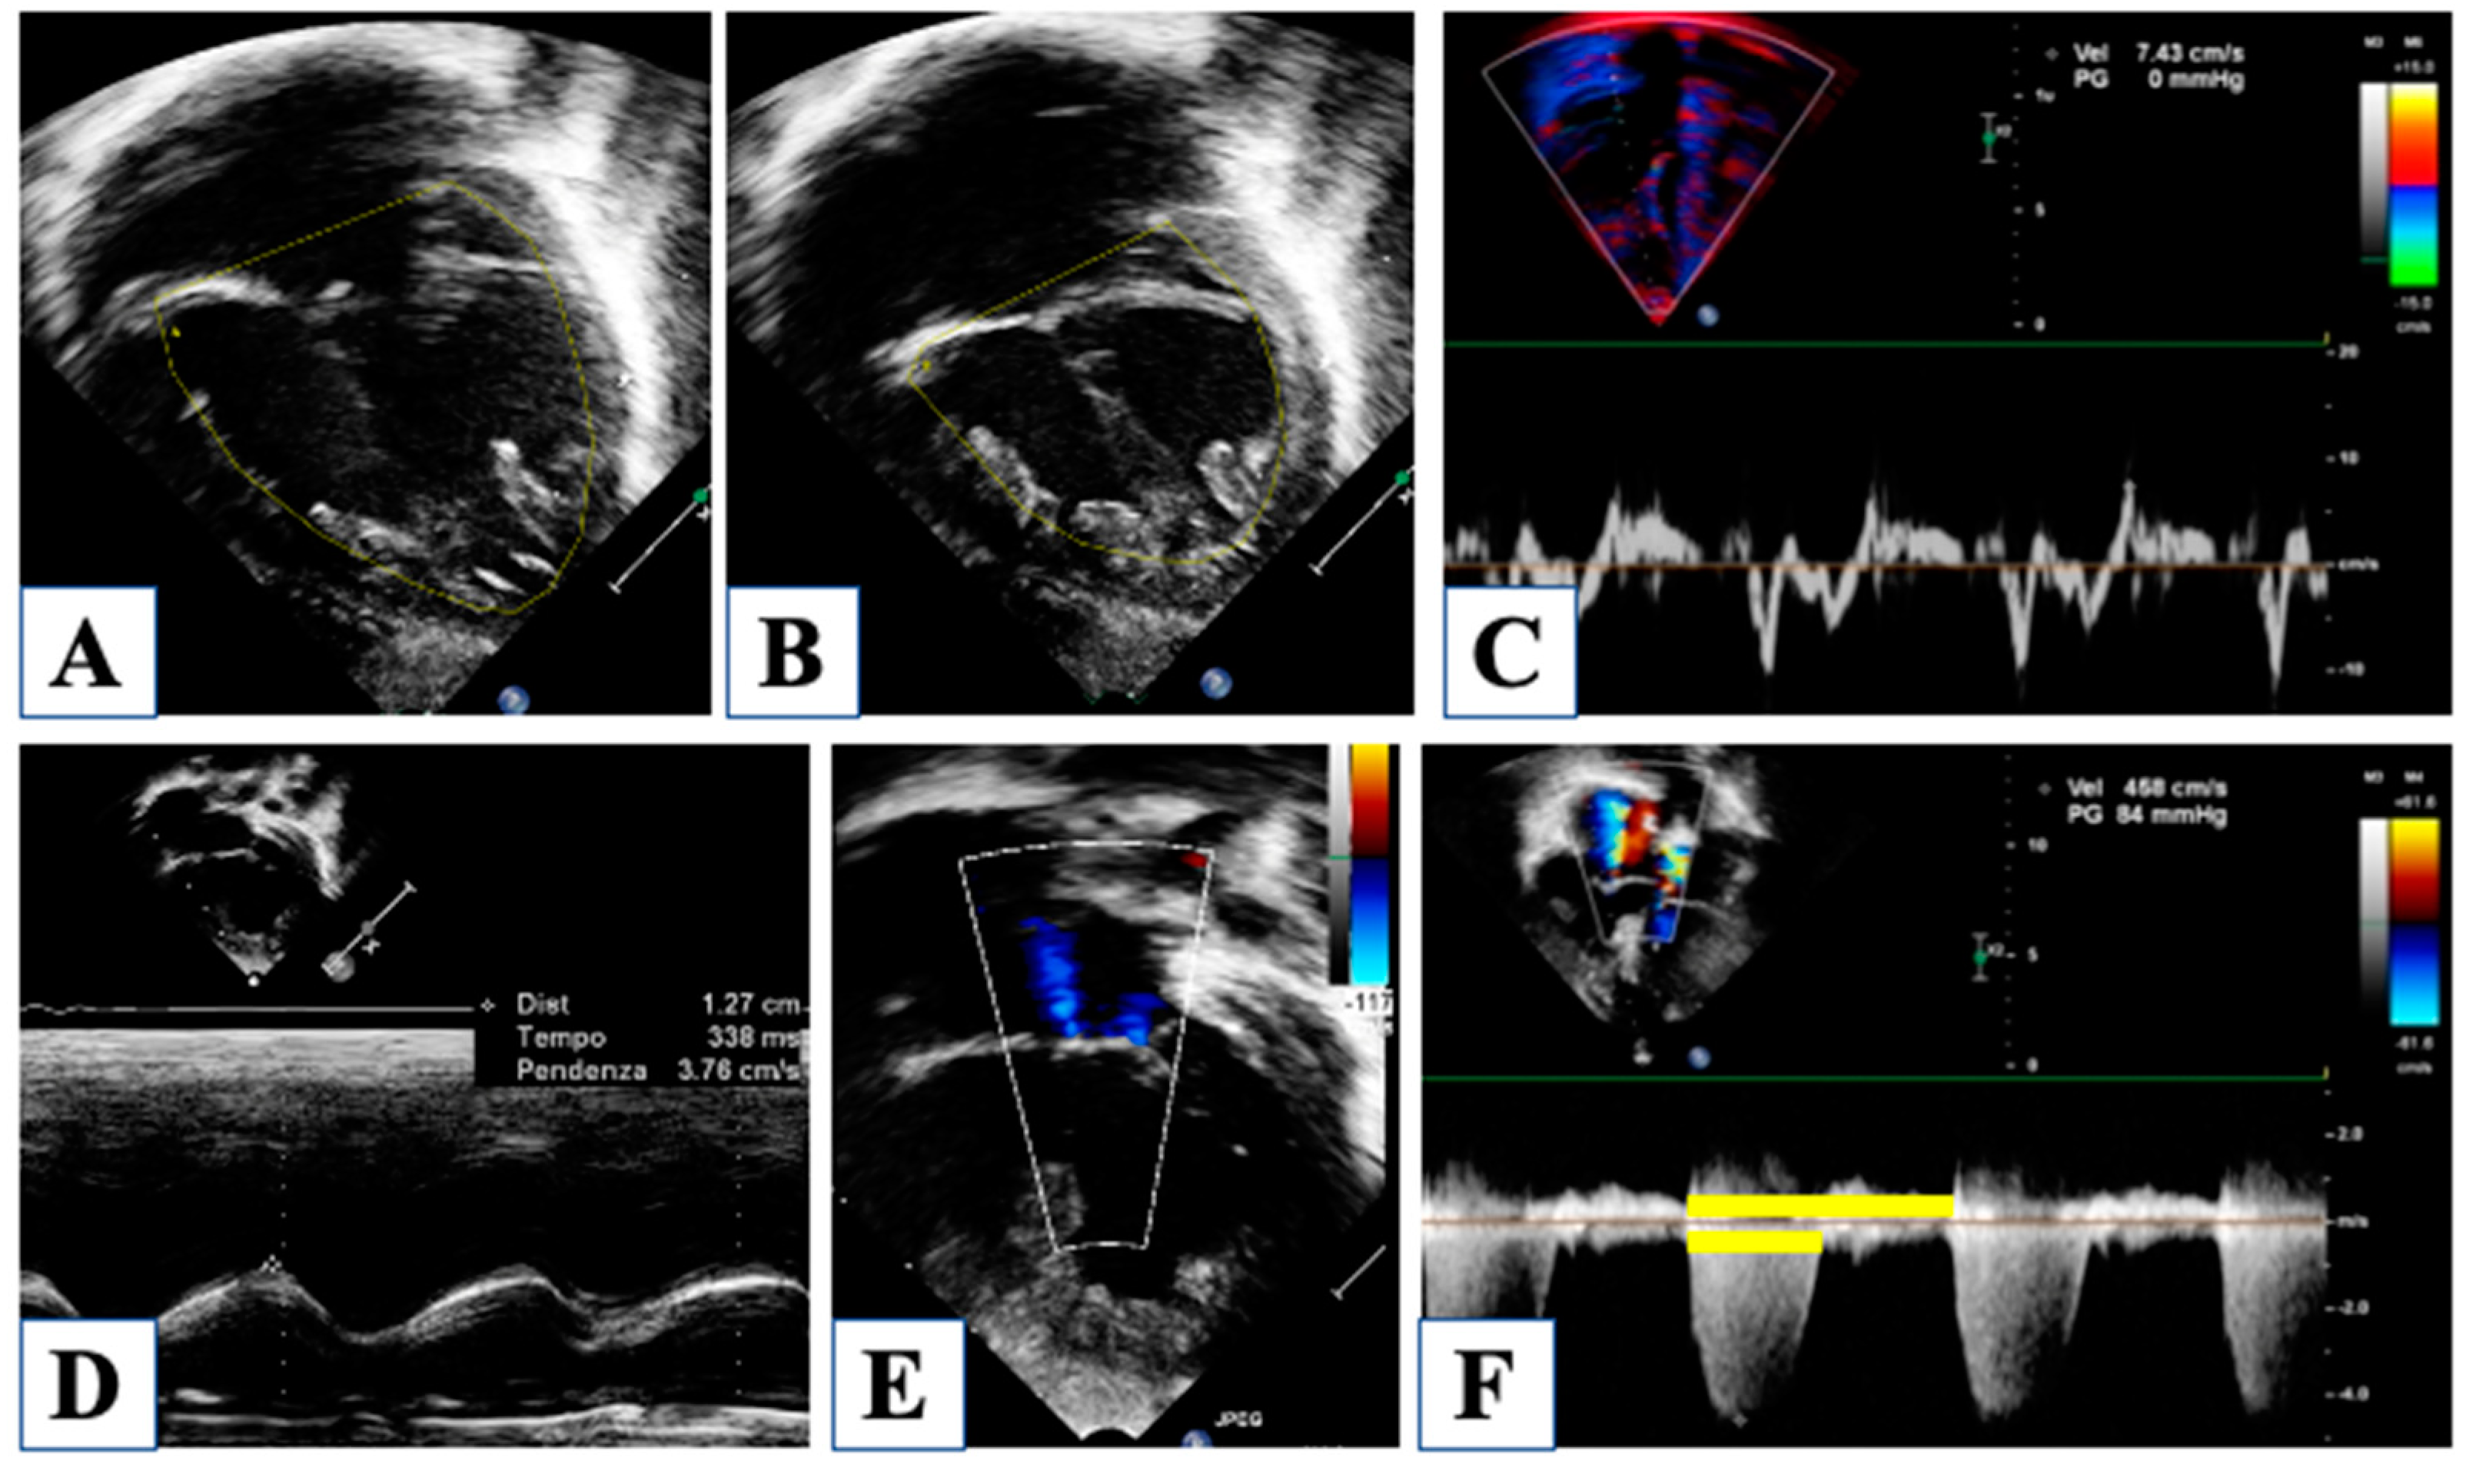

3. At Birth

4. Morphological Insights: The Borderline LV

| Oreto et al., 2023 | [16] | Pre-stage I | Left ventricle, aortic and mitral valves, long axis ratio | Aortic annulus, mitral annulus, aortic root, left ventricular/heart long axis, left ventricular volumes, and mass | Evaluation of the borderline left ventricle |